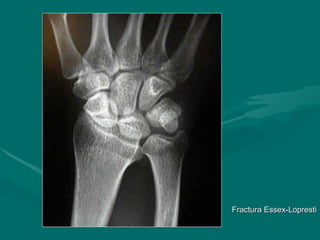

Fractura Essex-Lopresti

• Fractura conminuida de la cabeza

Fractura conminuida de la cabeza

radial asociada con subluxacion de la

articulacion radioulnar distal

• Usualmente asociado con la desviacion

Usualmente asociado con la desviacion

radial de la mano

• En las fracturas conminutas

En las fracturas conminutas

de la cabeza de radio debe ser

indispensable una examen radiológico

de la muñeca

Fractura Essex-Lopresti Fractura Essex-Lopresti •Fractura conminuida de la cabeza Fractura conminuida de la cabeza radial asociada con subluxacion de la radial asociada con subluxacion de la articulacion radioulnar distal articulacion radioulnar distal • Usualmente asociado con la desviacion Usualmente asociado con la desviacion radial de la mano radial de la mano • En las fracturas conminutas En las fracturas conminutas de la cabeza de radio debe ser de la cabeza de radio debe ser indispensable una examen radiológico indispensable una examen radiológico de la muñeca de la muñeca